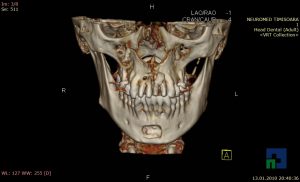

- Diagnosticul fracturilor:

- Unice

- Multiple

- Cu înfundare

- Complexe cranio-sinusale

- Complexe cranio-etmoidale

- Complexe cranio-orbitare

- Complexe cranio-faciale